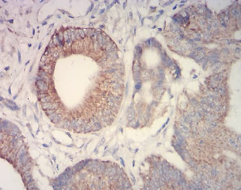

IHC    1/200 - 1/1000